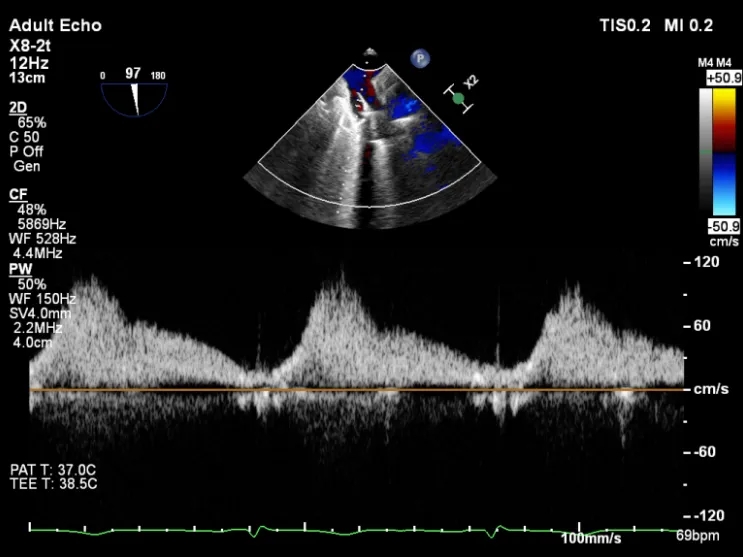

四条肺静脉均可测及收缩期反向血流

肺静脉收缩期逆流消失,频谱形态基本恢复正常